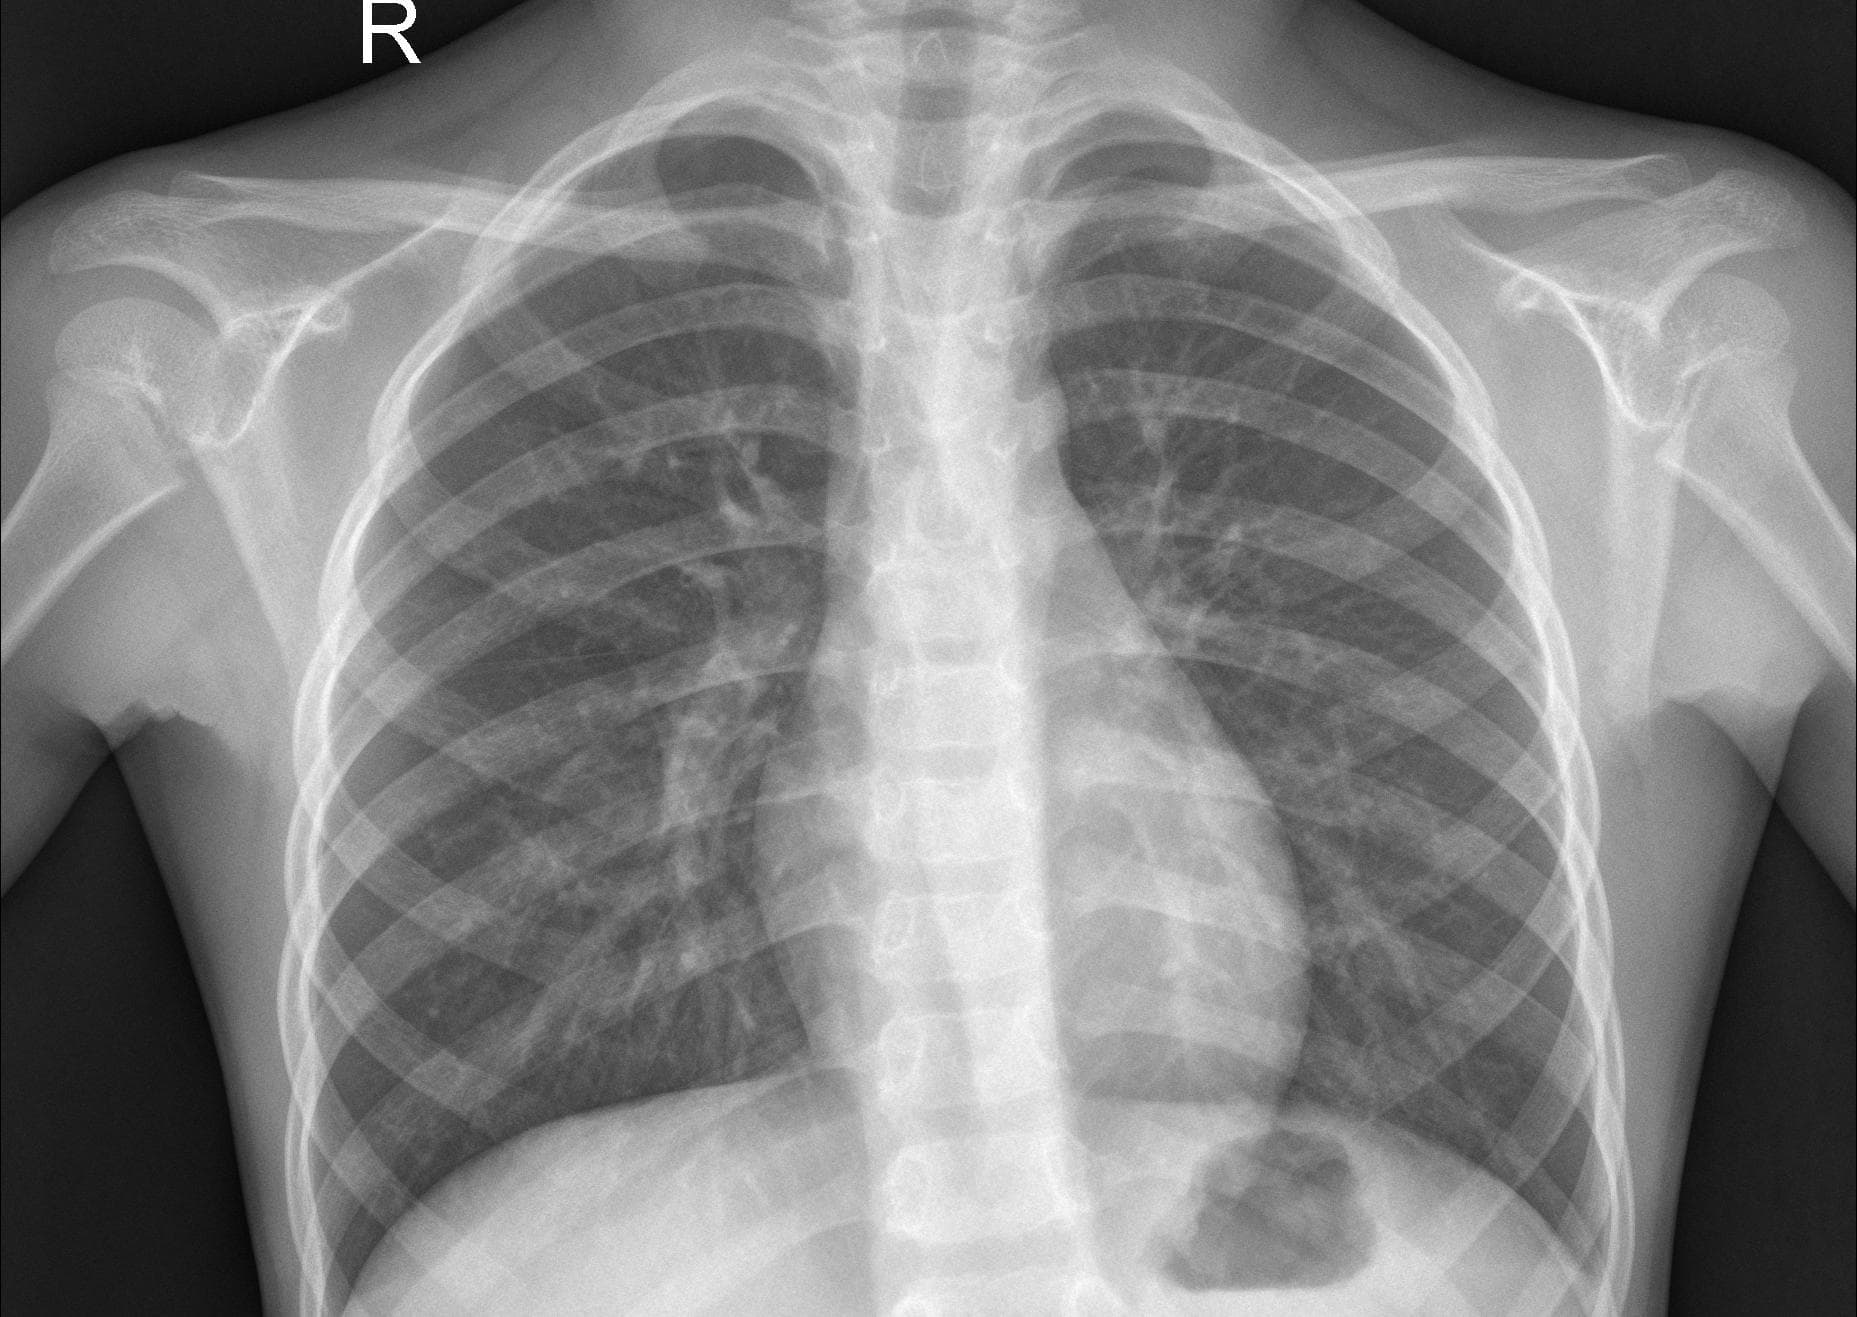

Custom CNN Model for Pheumonia Detection using Chest XRays

A lightweight domain specific CNN Model that aids in Pneumonia Detection by analysing the Chest X-Rays